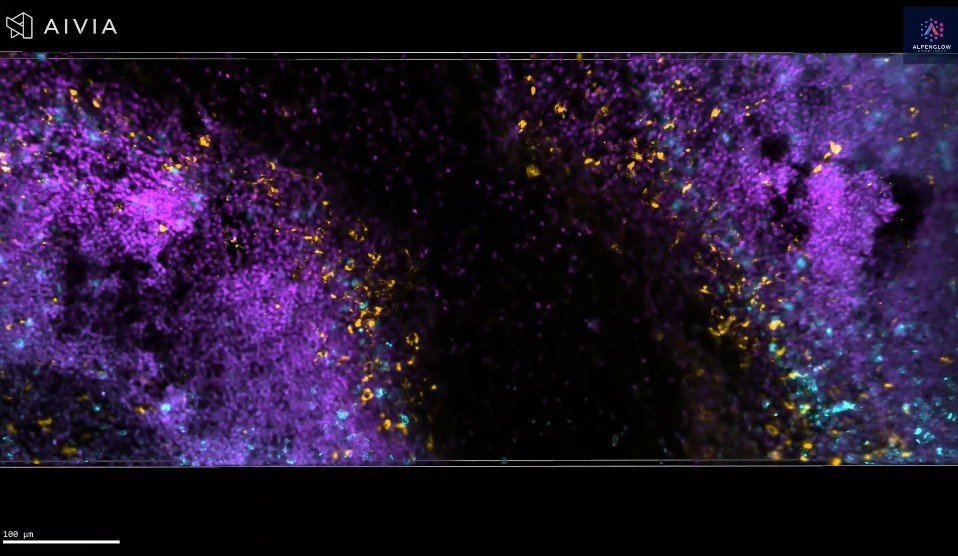

3D Imaging of Human Tonsil Tissue Highlighting Mast Cells with Tryptase Staining

3D view of human tonsil tissue stained with YO-PRO-1 and Tryptase, revealing mast cell distribution and spatial organization in unprecedented detail.